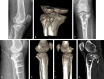

The posterior tibial plateau fracture is drawing increasing attention from orthopedists in recent years with the popularity of CT. However, due to the particular and severity of posterior tibial plateau fracture, there is still controversy in its classification and treatment. It is very difficult to achieve the ideal reduction and fixation by conventional techniques and approaches. The modified posterior approach is favorable for posterior tibial plateau fracture, but disadvantages remain. Recently, the lateral approach is applied by doctors. It is ideal for treatment of posterior tibial plateau fracture. Because of the complexity of local anatomical structure, the operative management of posterior tibial plateau fractures is a contentious issue as revealed in the recent surge of published literature addressing the surgical approach. This review mainly summaries the diagnosis, classification and surgery of the posterior tibial plateau fractures.